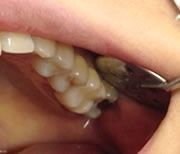

審美治療

審美治療を成功させる重要な要素は、意外かもしれませんが被せ物の色調や形態ではなく、周囲の歯肉と被せ物の境目の調和自然です。

被せ物と歯の境目の小さな段差やほんのわずかなミクロのセメントの取り残しが細菌の巣になって歯肉の炎症を引き起こし、徐々に歯肉を下げてしまい、数年後には境目が見えて審美治療の失敗となります。

肉眼では確認しづらい部分も、マイクロスコープは手に取るように見られます。